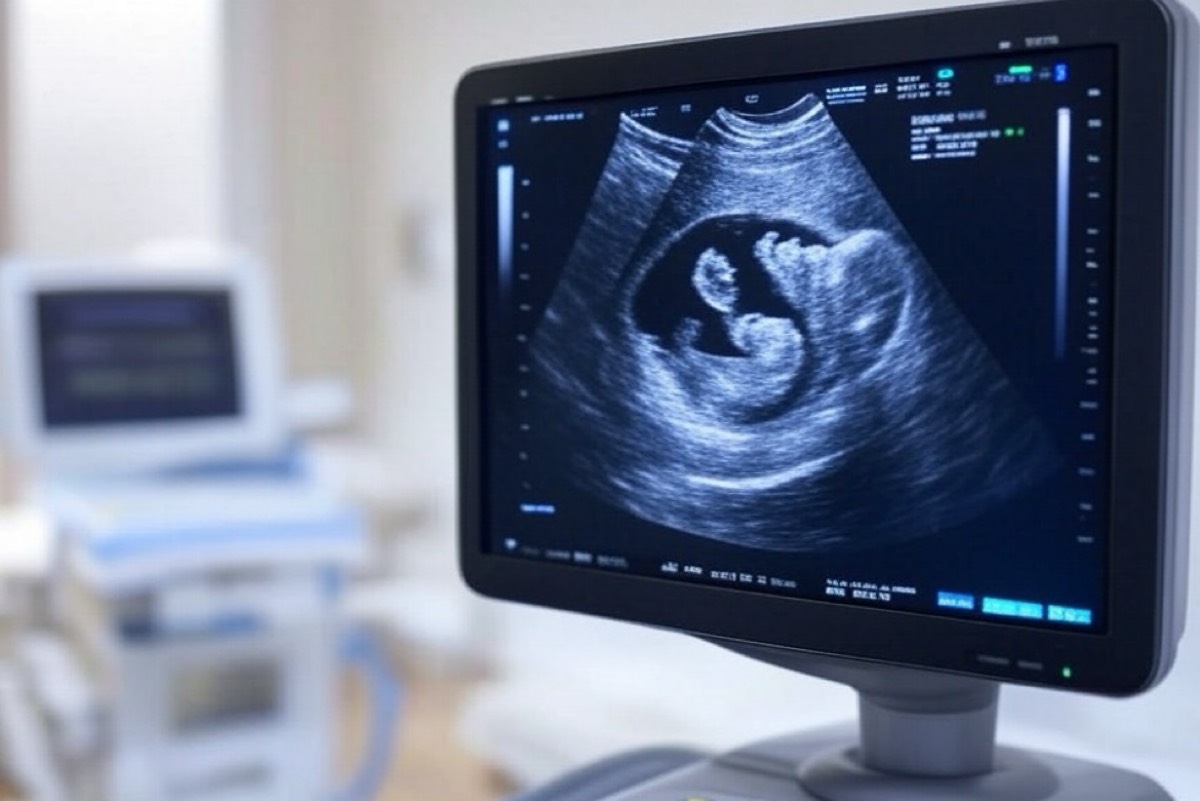

أكدت الدكتورة مها النمر، استشارية أمراض النساء، على الدور المحوري الذي تلعبه الأشعة الصوتية في ضمان سلامة الأم والجنين طوال فترة الحمل.

وأوضحت أن هذه التقنية التصويرية غيرinvasive توفر معلومات قيمة للأطباء والأمهات على حد سواء، مما يساعد في الكشف المبكر عن أي مشكلات صحية واتخاذ القرارات المناسبة.

وتعتبر الأشعة الصوتية من الأدوات الأساسية في رعاية الحمل، حيث توفر معلومات قيمة للأطباء والأمهات على حد سواء، مما يساعد في اتخاذ القرارات المناسبة لضمان صحة الأم والجنين طوال فترة الحمل.